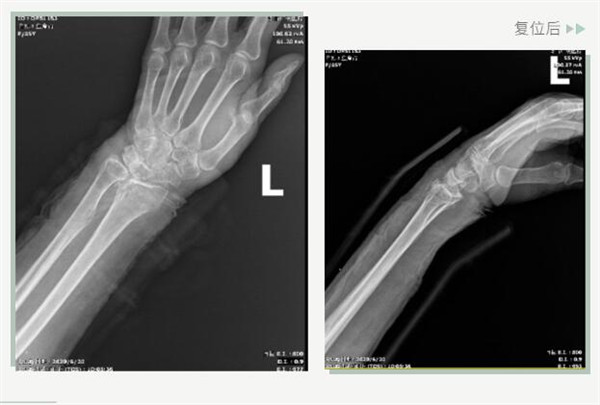

復位前

25日當天,莊阿婆來到危立軍副院長門診,經(jīng)拍片顯示,莊阿婆左橈骨遠端粉碎性骨折,左髂骨至髖臼后緣及恥骨下支骨折??紤]到莊阿婆年紀較大,基礎病較多,難以經(jīng)受手術創(chuàng)傷,傳統(tǒng)手法復位更為合適。推、拽、按、捺……經(jīng)過危立軍副院長一番手法復位后,再次拍片顯示莊阿婆橈骨遠端骨折端復位位置良好,莊阿婆及其家人感到非常滿意。

復位后